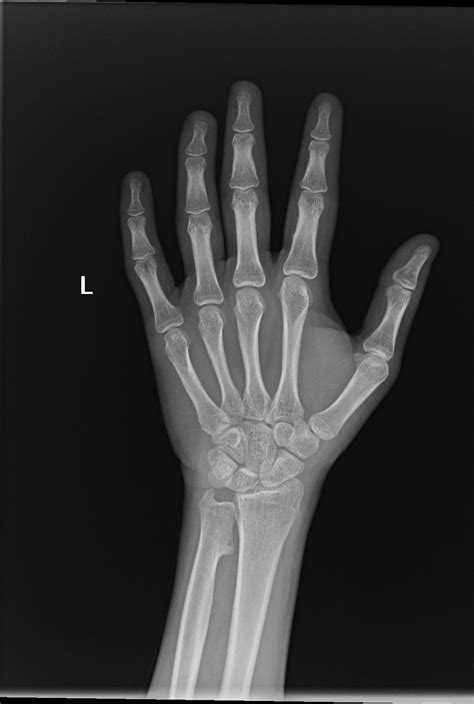

A Normal Wrist Xray is a radiographic image of the wrist that shows the bones, joints, and surrounding soft tissues. It is commonly used to diagnose fractures, dislocations, and other abnormalities in the wrist area. The procedure is non-invasive and relatively quick, making it a preferred method for initial assessments.

4. Multiple images are taken from different angles to provide a comprehensive view.

A Normal Wrist Xray can help diagnose a variety of conditions, including:

• Fractures: Common in the scaphoid, radius, and ulna bones.

• Dislocations: Often involving the lunate or other carpal bones.

• Arthritis: Including osteoarthritis and rheumatoid arthritis.

• Carpal Tunnel Syndrome: Although not directly visible, X-rays can rule out other causes of wrist pain.

• Bone Tumors: Benign or malignant growths in the wrist bones.